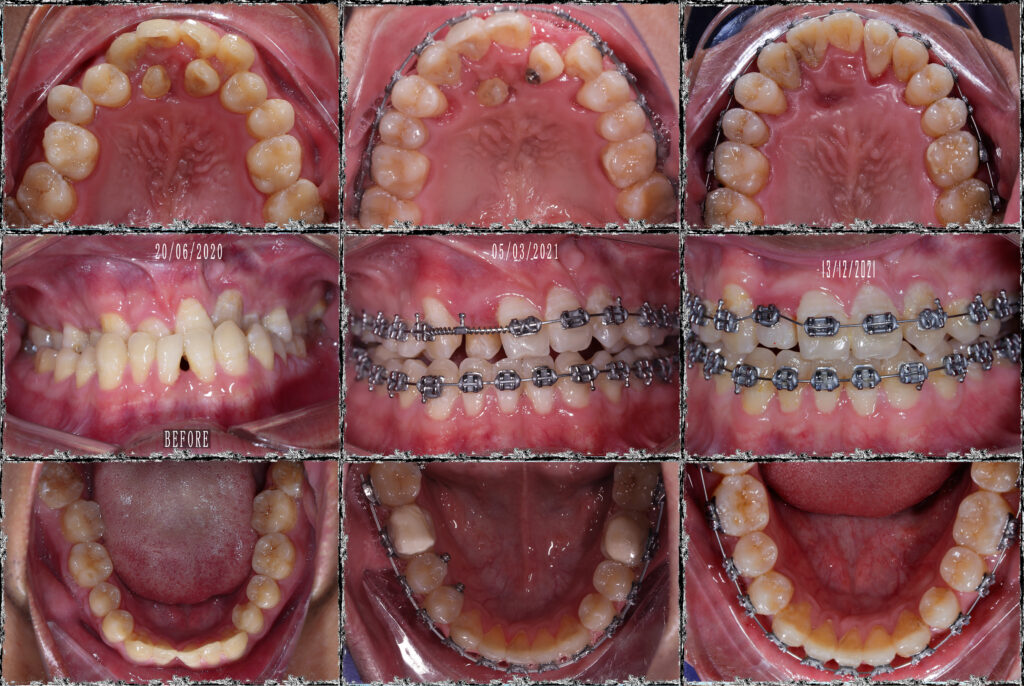

BN khớp cắn hạng 3, hàm trên nằm trọn trong hàm dưới. Hàm trên cực hẹp. Chỉ định nong hàm với ốc nong nhanh và dây Damon. Dựng trục răng 7 hàm dưới, torque lại trục răng hàm trên, giải “hẹp” hàm trên, kéo răng lệch phía khẩu cái ra ngoài. Giải khớp cắn ngược răng cửa, cắn kéo R7, tất cả dùng dây cung thẳng liên tục.